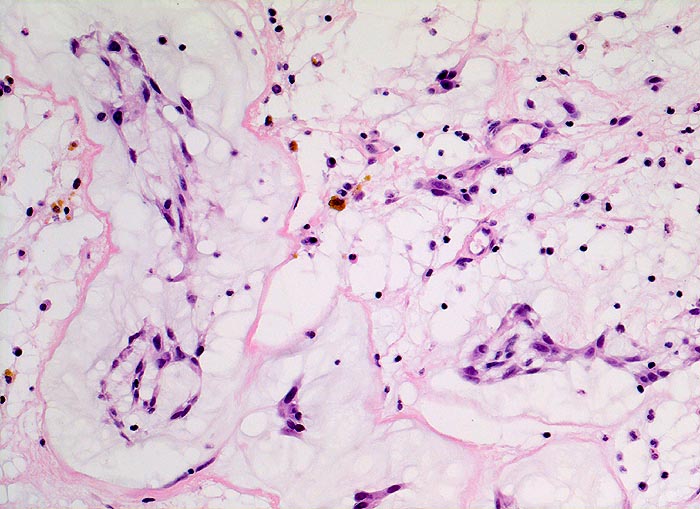

Vorhofmyxom

Makroskopie

Befund

Pathologischer Befund